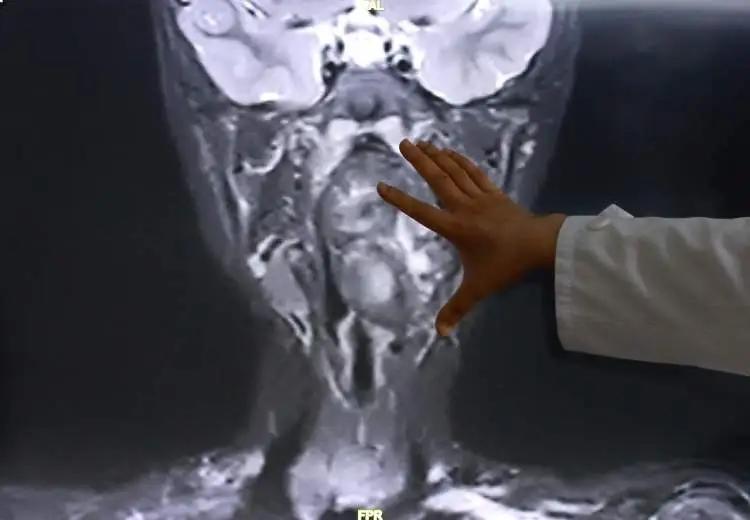

近日,小亮来到复旦大学附属儿科医院就诊,经增强CT及磁共振检查,明确小亮所患的肿瘤约7×3.5×3cm,犹如“拳头”般大小。专家表示,该肿瘤紧邻颈内动静脉并将血管明显向外推移,肿瘤向咽喉腔内隆起,占据大部分口咽及下咽腔,严重压迫声门,随时可能发生窒息。

鉴于病情危重、解剖结构复杂,儿科医院耳鼻咽喉头颈外科立即联合麻醉科、重症医学科的专家开展多学科评估与术前讨论,制定经口微创、精准安全的个体化手术方案。因手术风险极高,为了避免术中可能发生的意外情况,救治团队同时制定了详尽的备选手术方案。

在做好充分准备后,小亮被推进手术室。耳鼻咽喉头颈外科主刀专家陈超团队在精准解剖、全程保护血管神经的前提下,采用经口腔咽壁切开联合内镜辅助技术,历时近3小时顺利切除巨大肿瘤。术后,患儿转入重症医学科进行监护,平稳度过水肿期与感染关,未出现任何并发症,于20日转回普通病房。小亮术后恢复顺利,近日已康复出院。